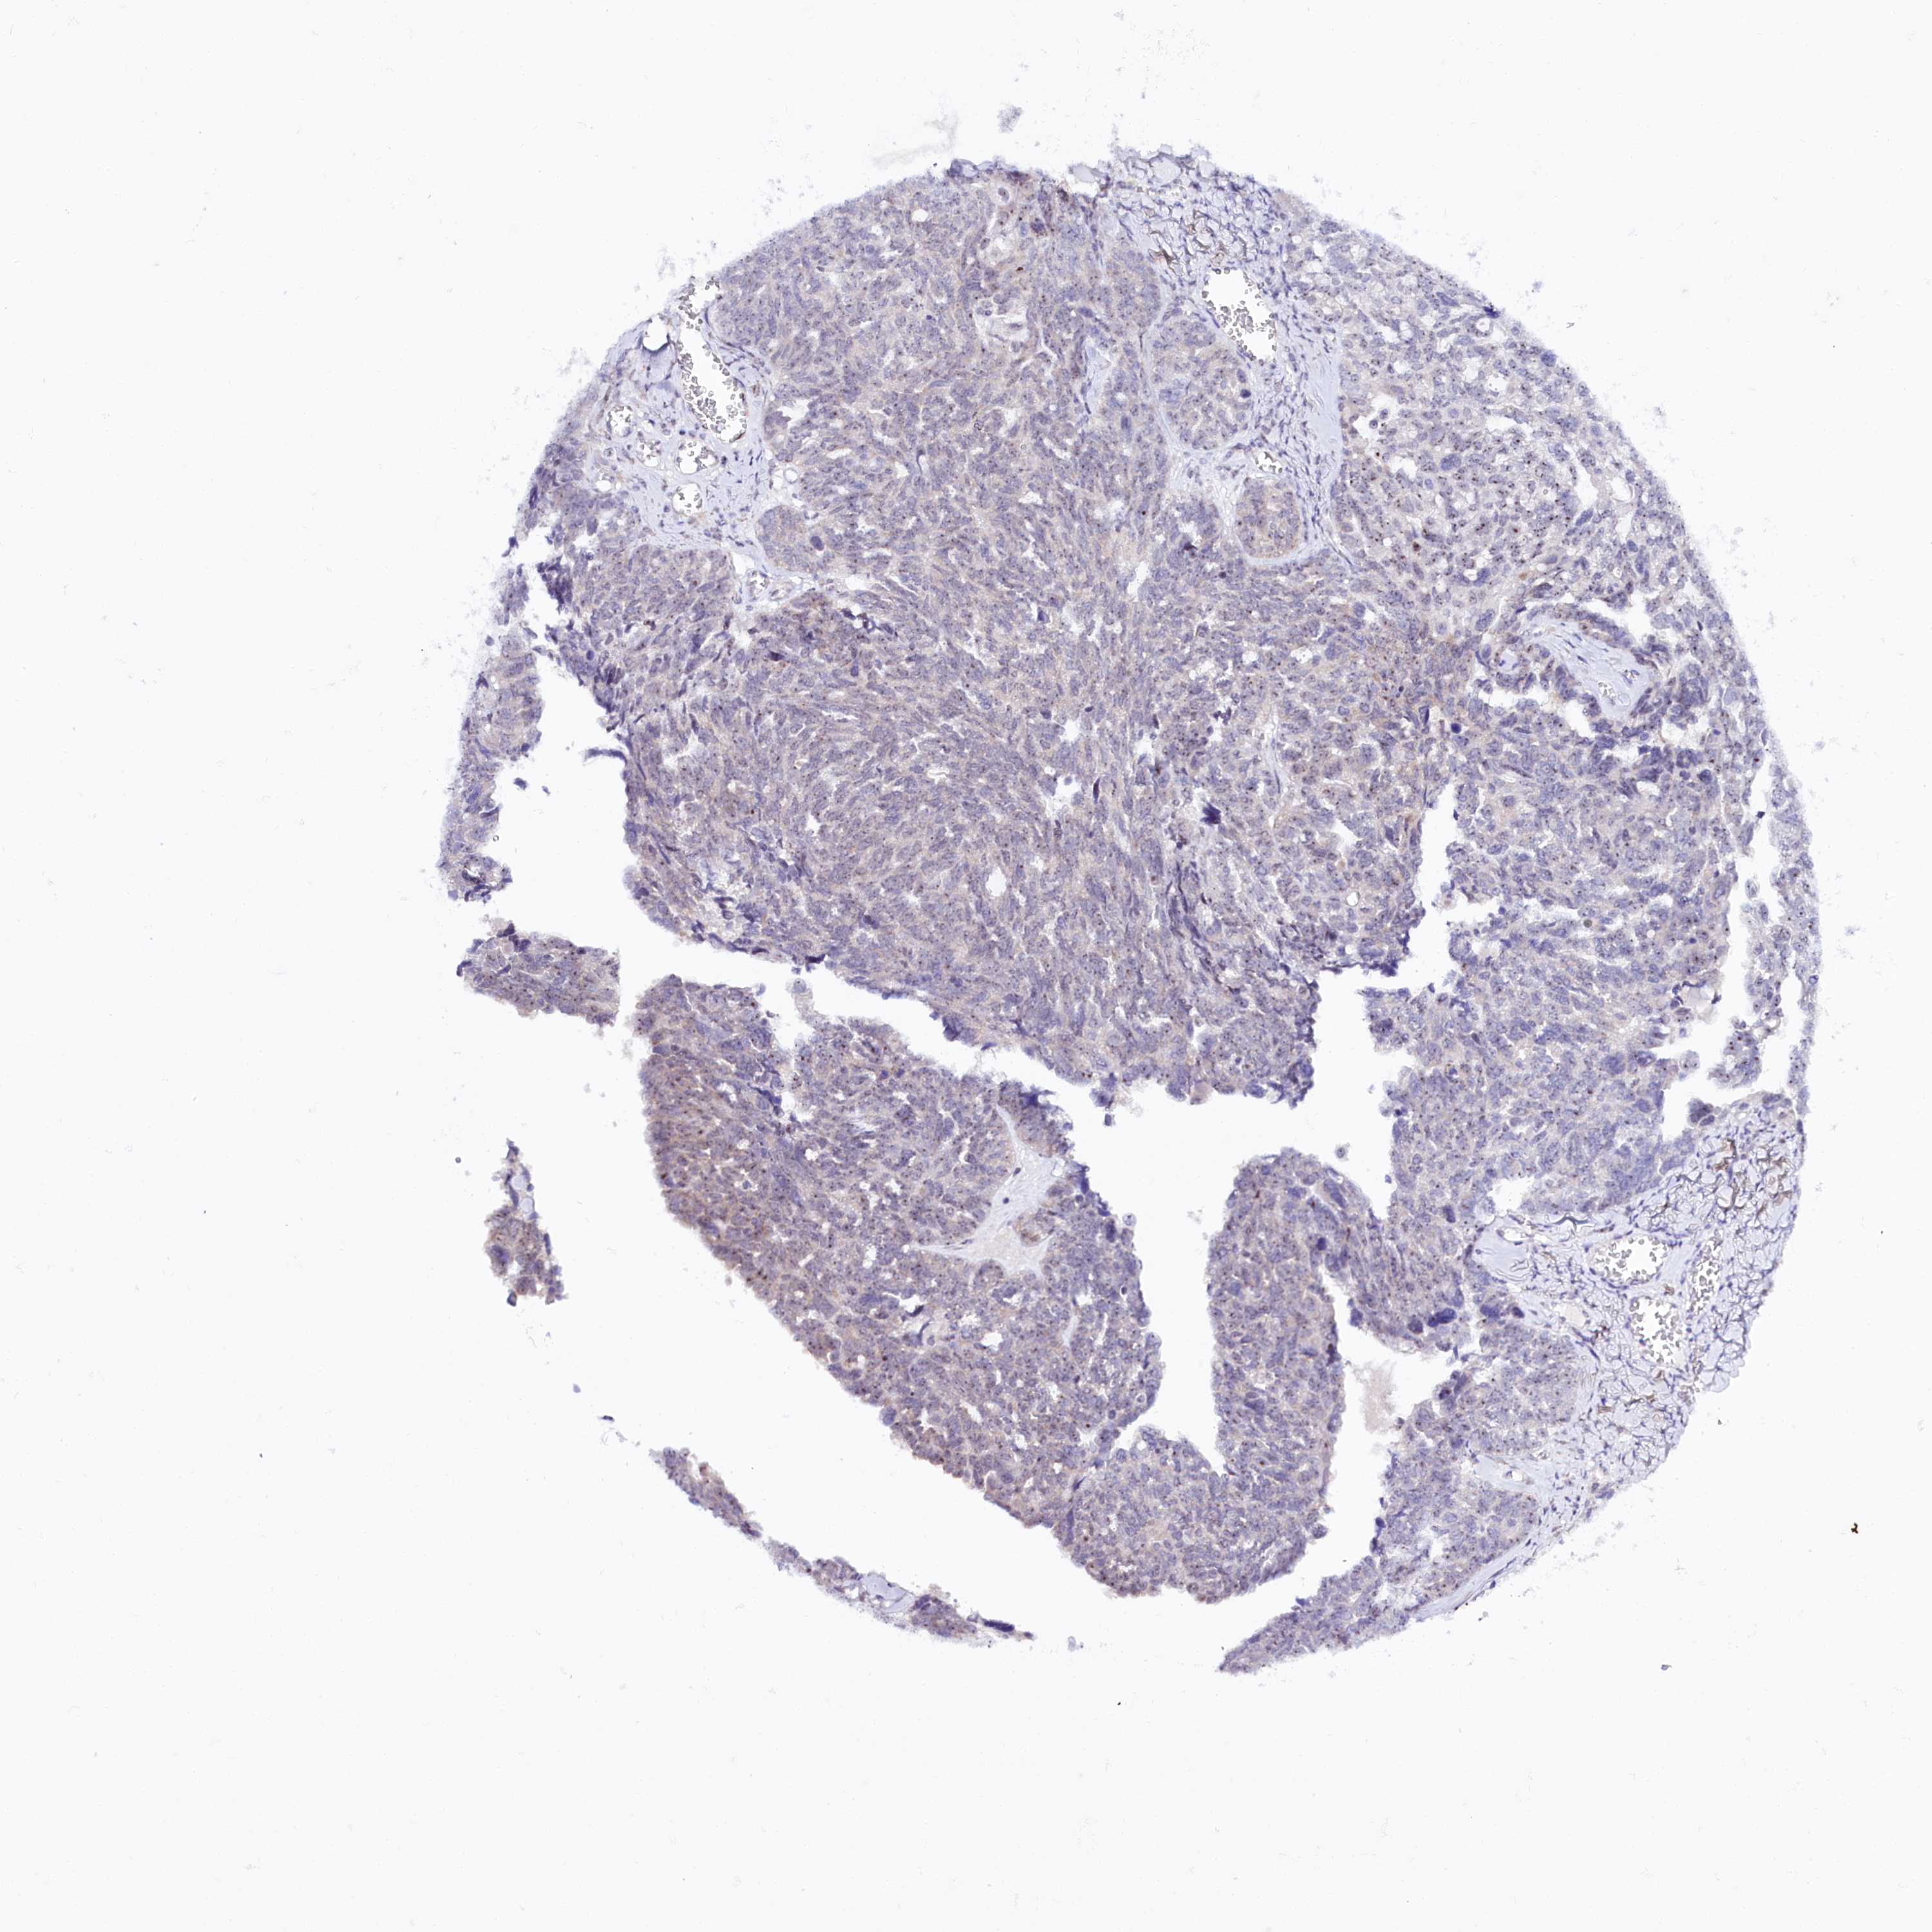

OVARIAN CANCER - Protein expressioni

A mouse-over function shows sample information and annotation data. Click on an image to view it in a full screen mode. Samples can be filtered based on level of antibody staining by selecting one or several of the following categories: high, medium, low and not detected. The assay and annotation is described here.

Note that samples used for immunohistochemistry by the Human Protein Atlas do not correspond to samples in the TCGA dataset.

Antibody stainingi

Antibody staining in the annotated cell types in the current human tissue is reported as not detected, low, medium, or high, based on conventional immunohistochemistry profiling in selected tissues. This score is based on the combination of the staining intensity and fraction of stained cells.

Each image is clickable and will lead to virtual microscopy that enables deeper exploration of all samples and also displays staining intensity scores, fraction scores and subcellular localization as well as patient and tissue information for each sample.

Antibody HPA038860

Staining

High

Medium

Low

Not detected

Intensity

Strong

Moderate

Weak

Negative

Quantity

>75%

75%-25%

<25%

None

Location

Nuclear

Cytoplasmic/membranous

Cytoplasmic/membranous,nuclear

Cystadenocarcinoma, serous, NOS

Carcinoma, endometroid

Cystadenocarcinoma, mucinous, NOS

Carcinoma, NOS